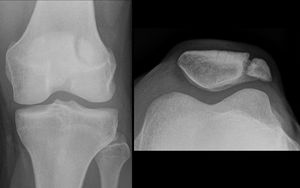

Interesting when I first saw it in my first time in practise. I thought it was fractured until I pain attention to the smoothed edges. Its an anatomical variation caused when the patella fails to ossiffy during development 🙂

No Ben, a Radiologist explained to me when I showed him the images. Btw !! Since We dont take images or pictures of our Real patients I had to find this pic on the internet that resembled the case/pt. I am a radiographer/ rad tech Ben :)

I know I am not educated or licensed to make any diagnoses on pathology so I Will only be posting cases that I have been Consulting with a radiologist and then radiographer/ rad.tech stuff :)